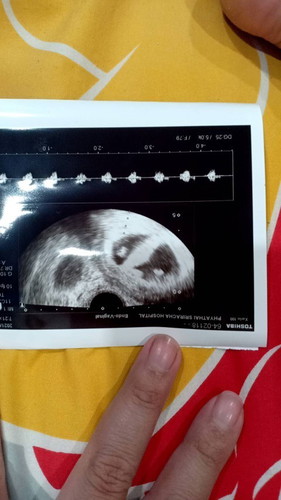

#ขอคำแนะนำหน่อยค่ะ พอดีต้องท้องแฝดค่ะ แต่มีเลือดทางช่องคลอด ไปพอคุณหมอ คุณหมอบอกเป็นแท้งคุกคาม แต่อันตาซาวด์น้องหัวใจยังเต้นอยู่ทั้ง 2 ดวง อายุครรภ์ 6 สัปดาห์ อย่างรู้ว่าน้องจะเป็นไรไหมค่ะ